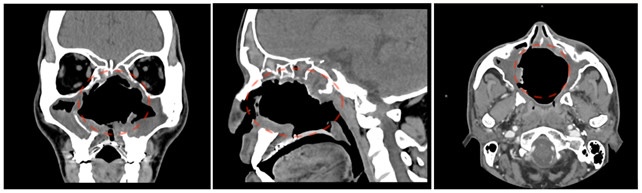

Dalle immagini preoperatorie si evince una voluminosa lesione espansiva, la massa misura circa 6 centimetri e occupa interamente le fosse nasali. A causa del tumore alcune strutture anatomiche risultano quasi irriconoscibili; i turbinati nasali, il setto nasale, le pareti ossee mediali dei seni mascellari, il palato duro, in quanto infiltrate dalla neoplasia.